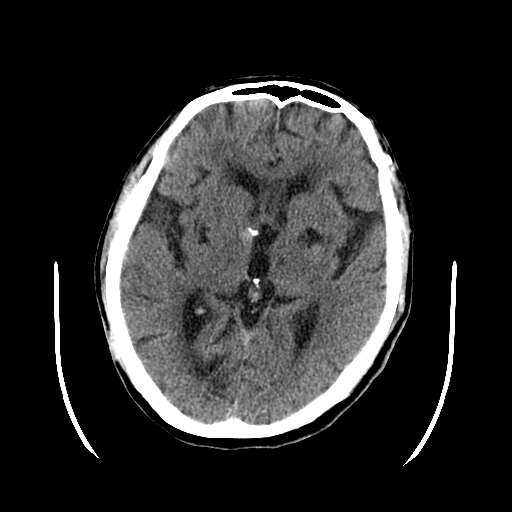

考虑:1、中脑右侧、右侧小脑半球、双侧丘脑缺血性脑梗塞;

2、右侧后交通动脉动脉瘤;

3、双侧基底节区腔隙性脑软化灶;

考虑:1、中脑右侧、右侧小脑半球缺血性脑梗塞;

3、双侧基底节区\\双侧丘脑腔隙性脑软化灶;

4、脑白质稀疏症。